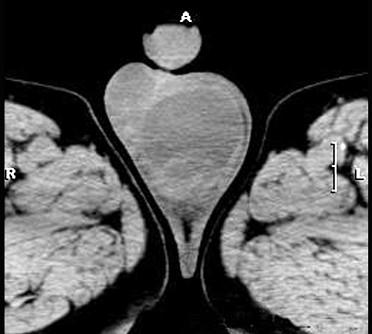

问题 男,2岁,阴囊囊性肿块,站立时明显增大,透光试验阳性,卧床时肿块缩小或消失,睾丸不能触及。应首先想到 ( )

选项 A、睾丸肿瘤 B、腹股沟斜疝 C、精索鞘膜积液 D、交通性鞘膜积液 E、睾丸鞘膜积液

答案 D